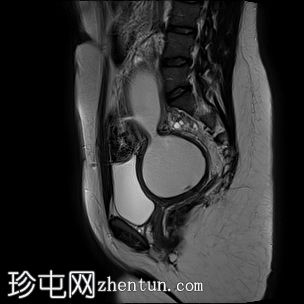

矢状位

T2加权像

子宫腔重复畸形,表现为两个子宫体和两个宫颈。

右侧宫颈和子宫腔明显扩张,内部血流信号显示中央狭窄,T1加权像呈高信号,T2加权像呈低信号,脂肪抑制序列图像上无信号下降,内部可见持续低信号灶。最大轴位和冠状位直径分别为约6.5 x 6.4 x 14.2 cm。可见该肿块向前压迫膀胱,向后推移右侧卵巢,并紧贴左侧宫颈。

左侧子宫系统未见扩张,未见与左侧子宫腔相通的迹象。

双侧重复子宫腔的交界区完整,未见明显的肌层局灶性病变。左侧子宫内膜厚度正常。

可见两个阴道腔,共同远端开口长1.6厘米。